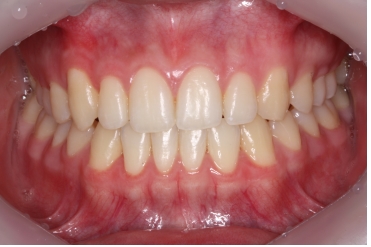

¿µ±¸Ä¡°¡ ¸ÍÃâÇÒ ½Ã±â°¡ µÇÁö ¾Ê¾Ò´Âµ¥ À¯Ä¡°¡ Èçµé·Á¼ ³»¿øÇÑ È¯ÀÚÀÔ´Ï´Ù.

ÀÌ¿Í °°ÀÌ °úÀ×Ä¡°¡ ¸ÍÃâÇÏ¸é¼ À¯Ä¡ÀÇ »Ñ¸®¸¦ Èí¼öÇØ¼ À¯Ä¡°¡ Á¤»óÀûÀÎ ½Ã±âº¸´Ù

»¡¸® ºüÁö°Ô µÇ´Â °æ¿ì°¡ Á¾Á¾ ÀÖ½À´Ï´Ù.

¾Õ´Ï°¡ ¹ú¾îÁö°í »ß¶Ô¾îÁ® Àִ ȯÀÚ¿¡¼ X-ray¸¦ ÃÔ¿µÇÏ¿´´õ´Ï °úÀ×Ä¡°¡ ¸Åº¹µÇ¾î ÀÖ´Â °ÍÀÌ º¸ÀÔ´Ï´Ù.

Ä¡¾Æ »Ñ¸® ¾ÕÂÊ¿¡ ¸Åº¹µÇ¾î ÀÖ´Â °úÀ×Ä¡·Î ÀÎÇØ ¾Õ´Ï »çÀ̰¡ ¹ú¾îÁö°í, ¿À¸¥ÂÊ ¾Õ´Ï°¡ »ß¶Ô¾îÁø ä·Î

¸ÍÃâÇÏ¿´½À´Ï´Ù.

ÀÌ·± °æ¿ì °úÀ×Ä¡¸¦ ¹ßÄ¡ÇÏ°í °£´ÜÇÑ ±³Á¤Ä¡·á·Î ¹®Á¦¸¦ ÇØ°áÇØÁÙ ¼ö ÀÖ½À´Ï´Ù.

°úÀ×Ä¡¸¦ ¹ßÄ¡ÇÑ ÈÄ¿¡ ±³Á¤Ä¡·á¸¦ ÅëÇØ ¹®Á¦¸¦ ÇØ°áÇØÁÖ¾ú½À´Ï´Ù.